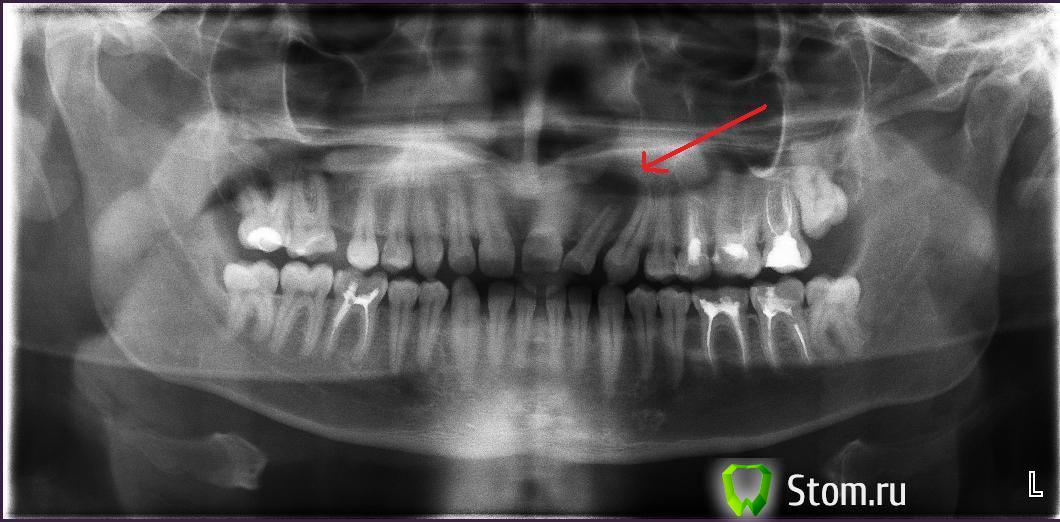

superman7 Опубликовано 27 февраля, 2012 Поделиться Опубликовано 27 февраля, 2012 (изменено) Здравствуйте Более месяца назад, на верхней десне выскочил свищ, размером не больше спичечной головки.Сделали несколько уколов антибиотика, полоскал, свищ прошел.Замечу, что зубы при этом не болели, не пломбированы После этого, свищ появился еще раз - появился утром, я пополоскал и через минут 20, все прошло. Врач говорит, что это, возможно киста и нужно резать десну. Подскажите, пожалуйста, что делать? Снимок прилагаю Спасибо,Александр Изменено 27 февраля, 2012 пользователем superman7 Ссылка на комментарий

Scrabble Опубликовано 27 февраля, 2012 Поделиться Опубликовано 27 февраля, 2012 Пока мы можем говорить только о радиолюцентной зоне в периапикальной области зуба 22. Диагноз "киста" обоснован только после гистологического исследования. Вмешательство эндодонтическое необходимо-если всё качественно, не исключено, что через год(в среднем) деструктивный процесс в костной ткани периапикальной зоны подвергнется инволюции. Оперативное вмешательство СЕЙЧАС нецелесообразно. 1 Ссылка на комментарий